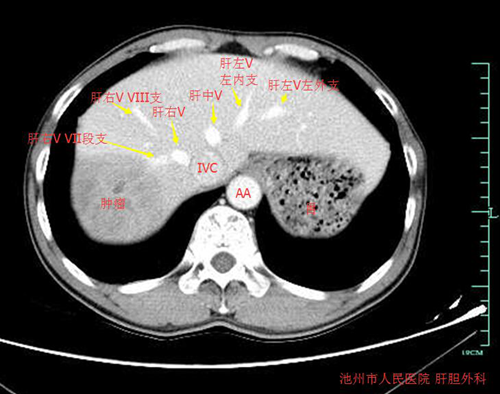

患者为48岁男性,来自贵池农村,二十余年前就曾被诊断为慢性乙肝“小三阳”,一直予随访观察,近两年来患者未规律随访,且患者长期抽烟,此次患者于入院前一天少量饮酒后发作右上腹部胀痛不适,持续不能缓解,于外地医院行B超提示肝脏混合回声巨大肿块。患者遂回家乡医院求进一步诊治,后于外院行CT检查提示右肝巨大占位,被告知手术难度大,建议上级医院就诊,遂转入我院。入院后予完善术前检查,进一步的检查提示患者右肝后叶巨大肿瘤,肿瘤最大径达10cm,结合病史及影像学特点,考虑为右肝巨大肝细胞肝癌。术前经过科室充分的讨论认为:患者左肝体积小,行右半肝切除有术后肝功能衰竭的风险,经过仔细的术前阅片分析患者肿瘤位于右肝后叶,右肝前叶正常,无转移子灶,行规则性右肝后叶切除能保障患者残肝体积,术后发生肝衰竭可能性小。但患者肿瘤巨大,与肝右静脉、门静脉右支及右肾上腺关系密切,且患者CT提示右肝前叶血液回流以肝右静脉为主,肝中静脉细小。行规则性右肝后叶切除既要保障肿瘤切缘阴性,又要保障右肝前叶肝组织血供及回流不受影响,且肝右后叶切除肝截面积大,手术难度很大。肝脏是人体腹腔内最大的实质性器官,血供极其丰富,组织脆性大,手术一旦损伤粗大血管,就有可能出现难以控制的大出血,甚至危及患者生命,对患者和医生都是一个巨大的考验。由孔胜兵主任医师、詹志林主治医师、佘刚住院医师组成的手术小组,术前进行了认真的讨论和周密的布署,为患者制定了选择性入肝血流阻断下的解剖性右肝后叶切除方案及根据术中肝脏硬化程度,肿瘤分布情况可能需要临时变化的手术预案。在麻醉科周孟虎主任的亲自保驾护航下,在手术室护理团队的通力配合下,孔胜兵主任利用娴熟的解剖技法,通过解剖出肝右静脉、肝右动脉、门静脉右支达到选择性控制右肝血供,再进一步地解剖出肝右后动脉、VI、VII段肝蒂,分别结扎后根据肝表面右后叶缺血线利用超声刀精细钳夹法离断肝实质,在肝实质内分别结扎分别结扎VI、VII段肝右静脉分支,成功保留肝右静脉主干和门静脉、肝右动脉右前支,成功完成了精准的右肝后叶切除,完整地切除了右肝肿瘤,手术历时约5小时,术中出血约200ml,未输血。术后在肝胆外科护理团队的精心照料下,患者恢复顺利出院。

术前影像学: